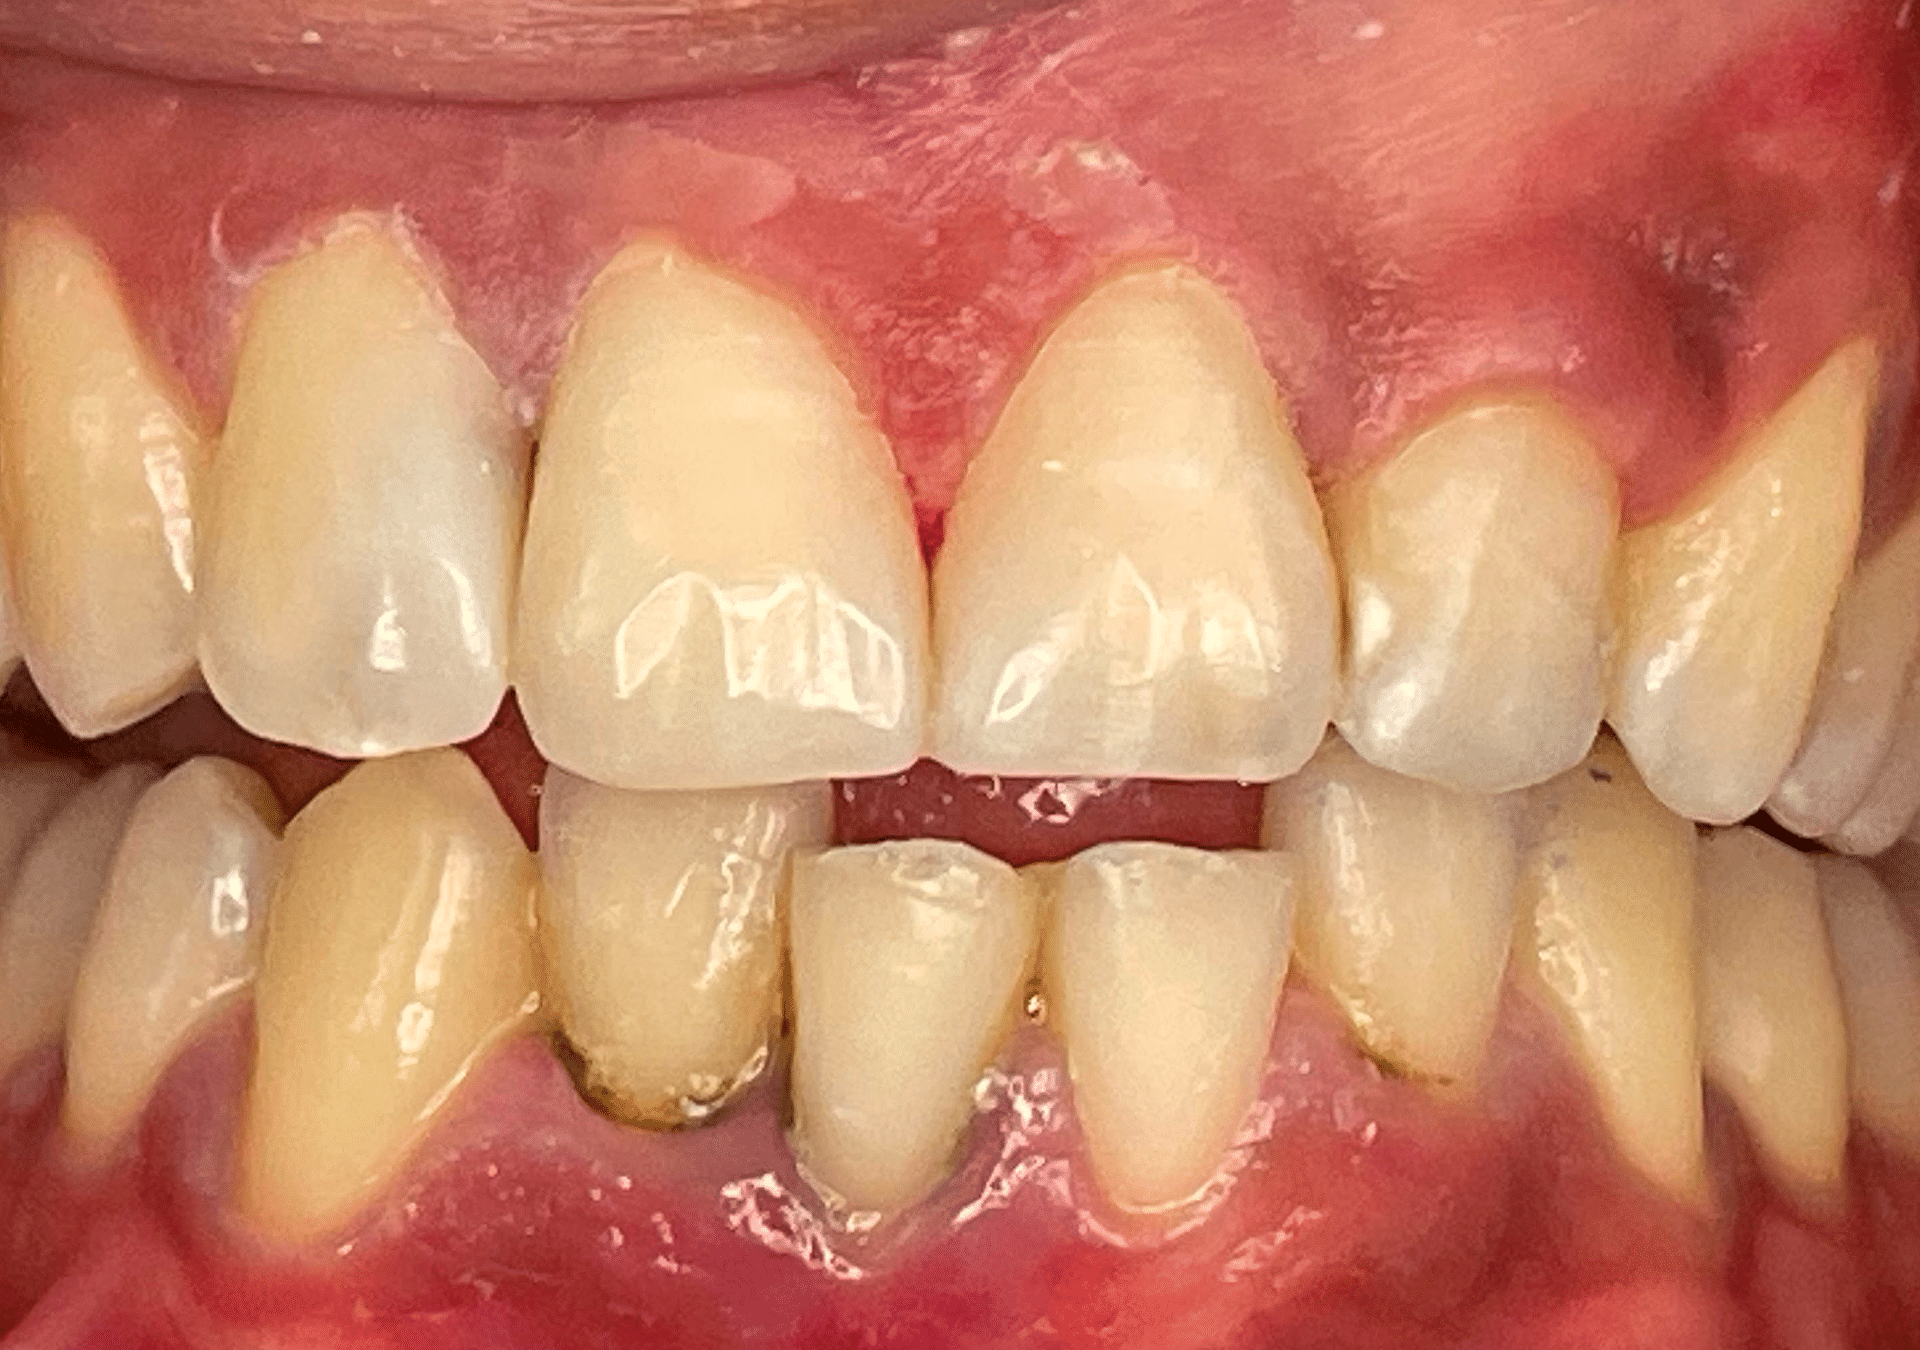

Caso 2

Rehabilitación con cerámica feldespática de paciente con amelogénesis imperfecta (esmalte defectuoso), eliminación de tinciones y protección superficies.